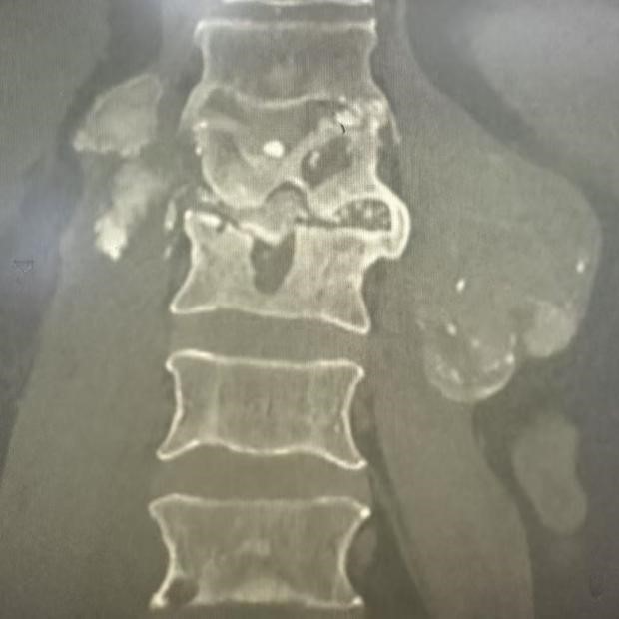

近日,山东省公共卫生临床中心脊柱感染外科谭洪栋主任团队在孙建民教授指导下成功完成全国首例后腹腔镜下腰椎感染病灶清除植骨融合手术。该手术采用先进的微创技术,与传统的OLIF手术相比,具有创伤小、出血少、术后恢复快、病人体验好等显著优势,标志着我国在腰椎感染微创治疗领域取得重大突破。

患者男性,72岁,因“腰椎感染伴腰大肌脓肿导致剧烈腰痛、活动受限”入院。传统的开放手术创伤大、恢复慢,患者痛苦不堪。经过详细评估和充分准备,山东省公共卫生临床中心脊柱感染团队决定采用创新的后腹腔镜技术为患者实施手术。

手术过程中,团队通过患者侧腹部四个不到1厘米的小切口,置入腹腔镜和精密手术器械。在高清放大的手术视野下,医生精准地清除了椎间及椎旁病灶,并进行椎间植骨融合。整个手术过程顺利,出血量低于10ml,远低于传统手术。